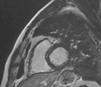

Case reportA 61-year-old man with no history of cardiac disease presented to a community hospital reporting typical chest pain 3hours in duration with more severe intensity in the last 30minutes. The initial standard 12-lead electrocardiogram (ECG) showed ST-segment elevation in leads V1–V5 and slight ST-segment elevation in the inferior leads (Fig. 1A). The patient was given 5000U of unfractionated heparin IV, 600mg clopidogrel oral loading dose and 300mg oral aspirin, and was transferred to our hospital for urgent catheterization. He arrived at our cath lab hemodynamically stable, with persistent chest pain. Coronary angiography, performed four and a half hours after symptom onset, showed a normal left coronary artery (Fig. 2) and patent main vessel of the codominant RCA. Left ventriculography was normal. Careful review of the coronary angiogram revealed proximal occlusion of the right ventricular (RV) branch of the RCA (Fig. 3A and B). The RV branch occlusion was managed with balloon dilation and stenting (2.0mm×12.0mm bare-metal stent at 16atm, Multi-Link Mini Vision®, Abbott Vascular, USA), resulting in resolution of the chest pain and ST-segment elevation (Figs. 1B and 3C). One hour after the procedure the patient experienced a new episode of chest discomfort and ST-segment changes similar to the initial ECG (re-elevation in leads V1–V4 and slight elevation in leads II, III, and aVF) (Fig. 1C). Emergency coronary angiography demonstrated acute stent thrombosis, which was probably related to previous inadequate stent covering of the proximal portion of the coronary plaque. Abciximab infusion was initiated, thrombus aspiration was performed and another proximal and overlapped bare-metal stent (2.25mm×12.0mm at 12atm, Multi-Link Mini Vision®, Abbott Vascular, USA) was implanted, again resulting in resolution of chest pain and ST-segment elevation. The peak troponin I level was 5.2ng/ml. The patient recovered without sequelae and was asymptomatic and fully active one month later. Contrast-enhanced magnetic resonance imaging (MRI) performed 30 days after presentation showed normal left ventricular function and normal right ventricular size and motion. No area of delayed hyperenhancement was visualized (Fig. 4).

Although it is usually considered that occlusion of a small nondominant right coronary artery is not associated with significant consequences, there are reports of cases presenting with sudden cardiac death.5 Importantly, there are also reports of sudden cardiac death in which autopsy confirmed the occlusion of a branch of the RCA causing isolated RVMI.6 Our case, to the best of our knowledge, is the first one reported of primary percutaneous coronary intervention treatment of an RV branch occlusion causing isolated acute RVMI and anterior ST-segment elevation. Acute stent thrombosis with recurrence of chest pain and anterior ST-segment re-elevation was successfully managed percutaneously. Revision of images of the first intervention showed that the proximal portion of the unstable coronary plaque was not covered by the stent. Another stent was implanted, proximal and overlapped to the previous one, to cover all the unstable plaque. Minimal myocardial necrosis was demonstrated by troponin assay and follow-up contrast-enhanced MRI showed no areas of delayed hyperenhancement in the right or left ventricles.